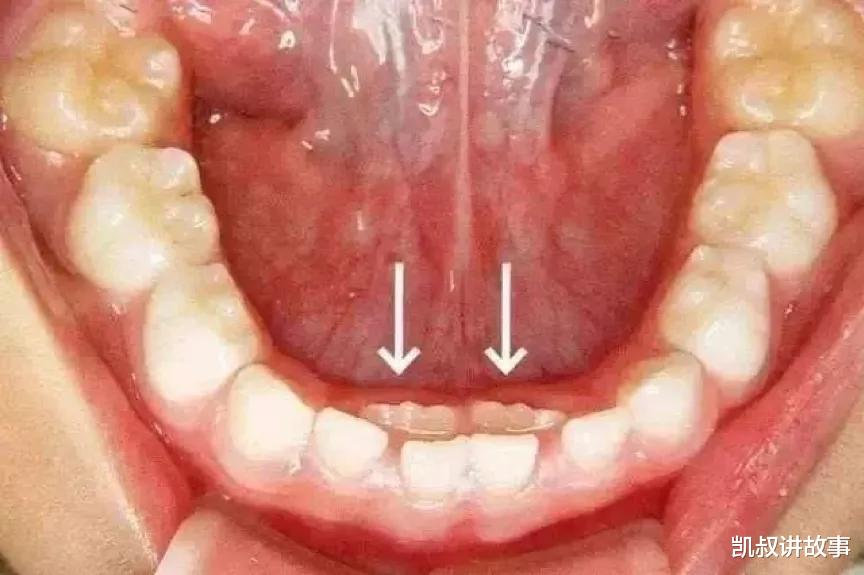

有的孩子长了双排牙 , 家人也迟迟没发现;

双排牙 。 图片来源:苏州口腔医院